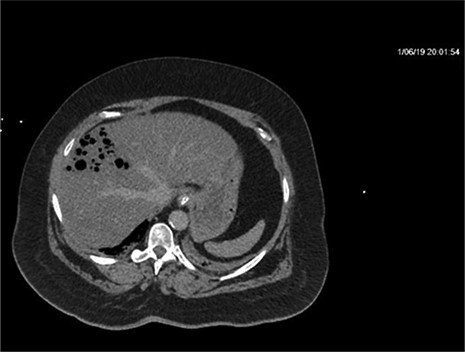

Repeat CT demonstrated a large amount of air within the liver parenchyma (Figs 2, 4, 6). Unfortunately, shortly after the repeat CT, the patient progressed to septic shock with cardiovascular collapse and was not able to be resuscitated with full advanced cardiac life support (ACLS) protocol. She expired within 16 h of initial presentation and within 24 h of symptom onset. Final blood culture results were positive for Clostridium perfringens.

Repeat imaging taken 13.5 h later which depicts many air bubbles in the liver parenchyma.